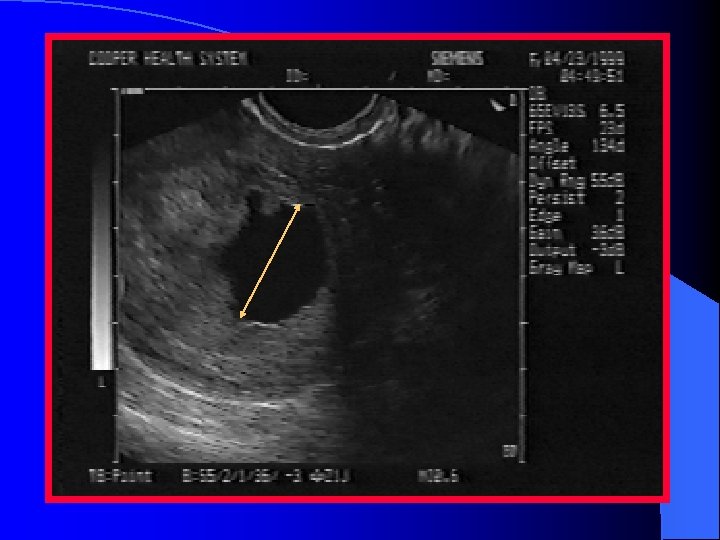

Abnormal IUP l. A GS larger than 10 -13 mm diameter(TV) or 20 mm (TA) without a yolk sac l A GS larger than 18 mm (TV) or 25 mm (TA) without a fetal pole l. A definite fetal pole without cardiac activity after 7 wks GA

Empty gestational sac